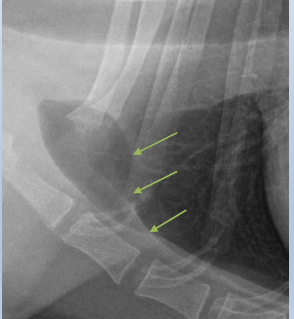

Feline